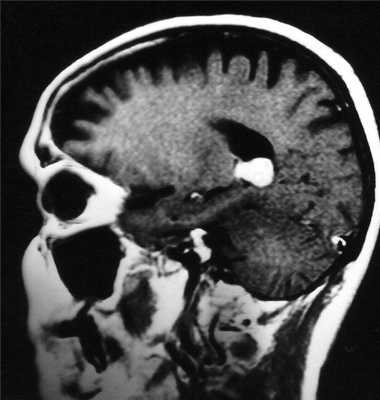

(а) MPT, Т2* GRE, аксиальный срез: определяются участки «выцветания» изображения, соответствующие участкам кальцификации гирального характера.

(б) Постконтратсное Т1-ВИ, режим подавления сигнала от жира, аксиальный срез: определяется контрастное усиление объемного образования серпантинного, гирального характера.

Других областей поражения или кожных аномалий выявлено не было. На данных снимках представлен случай предполагаемого (хирургически не подтвержденного) менингоангиоматоза.